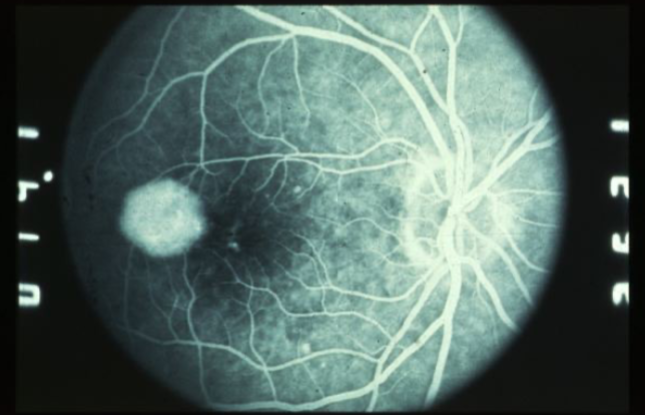

classic CNV/Gass type 2

CNVM

well defined hyperfluorescence

cartwheel or sea fan appearance

thought to break through RPE & staying sub-retinal

type 2 MNV

MNV is now b/t neurosensory retina & RPE making the IVFA more obvious & well defined

IVFA shows lacy, well-group area of neovascularization

hyperfluorescent early in study

late leakage

lacy early fill of the MNV during the choroidal & arterial filling phase

may have hypofluorescence corresponding to RPE hyperpigmentation & blood in the outline of the MNV

progressive hyperfluorescence throughout the FA w/o leakage of the margins of the MNV